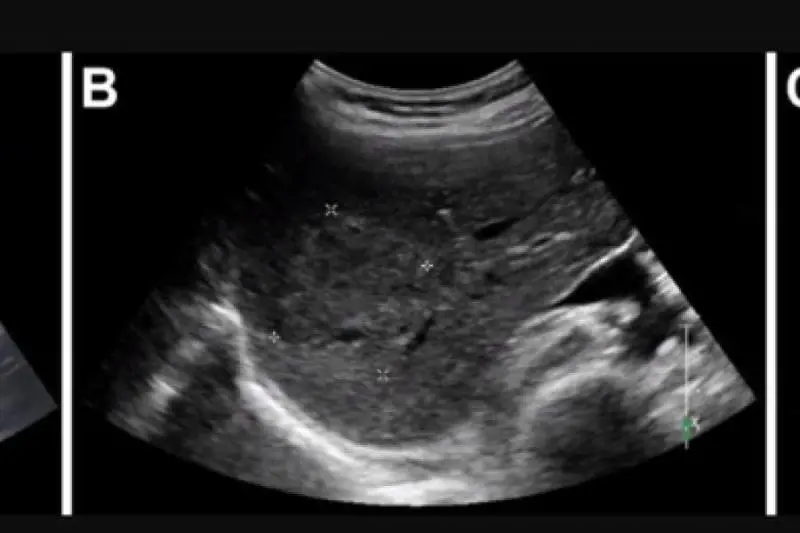

È già ben noto, in letteratura, qual è il ruolo della cirrosi epatica nel successivo sviluppo del tumore. Con questo termine di intende un diffuso "sovvertimento della struttura interna del fegato" che ha origine un'enorme quantità di tessuto epatico normale viene sostituito in modo permanente da tessuto cicatriziale, non funzionante", spiegano gli esperti nel Manuale Msd. Adesso, però, un nuovo approccio scientifico è partito dallo studio di questa patologia e qual è la sua progressione per comprendere il futuro sviluppo del tumore al fegato.